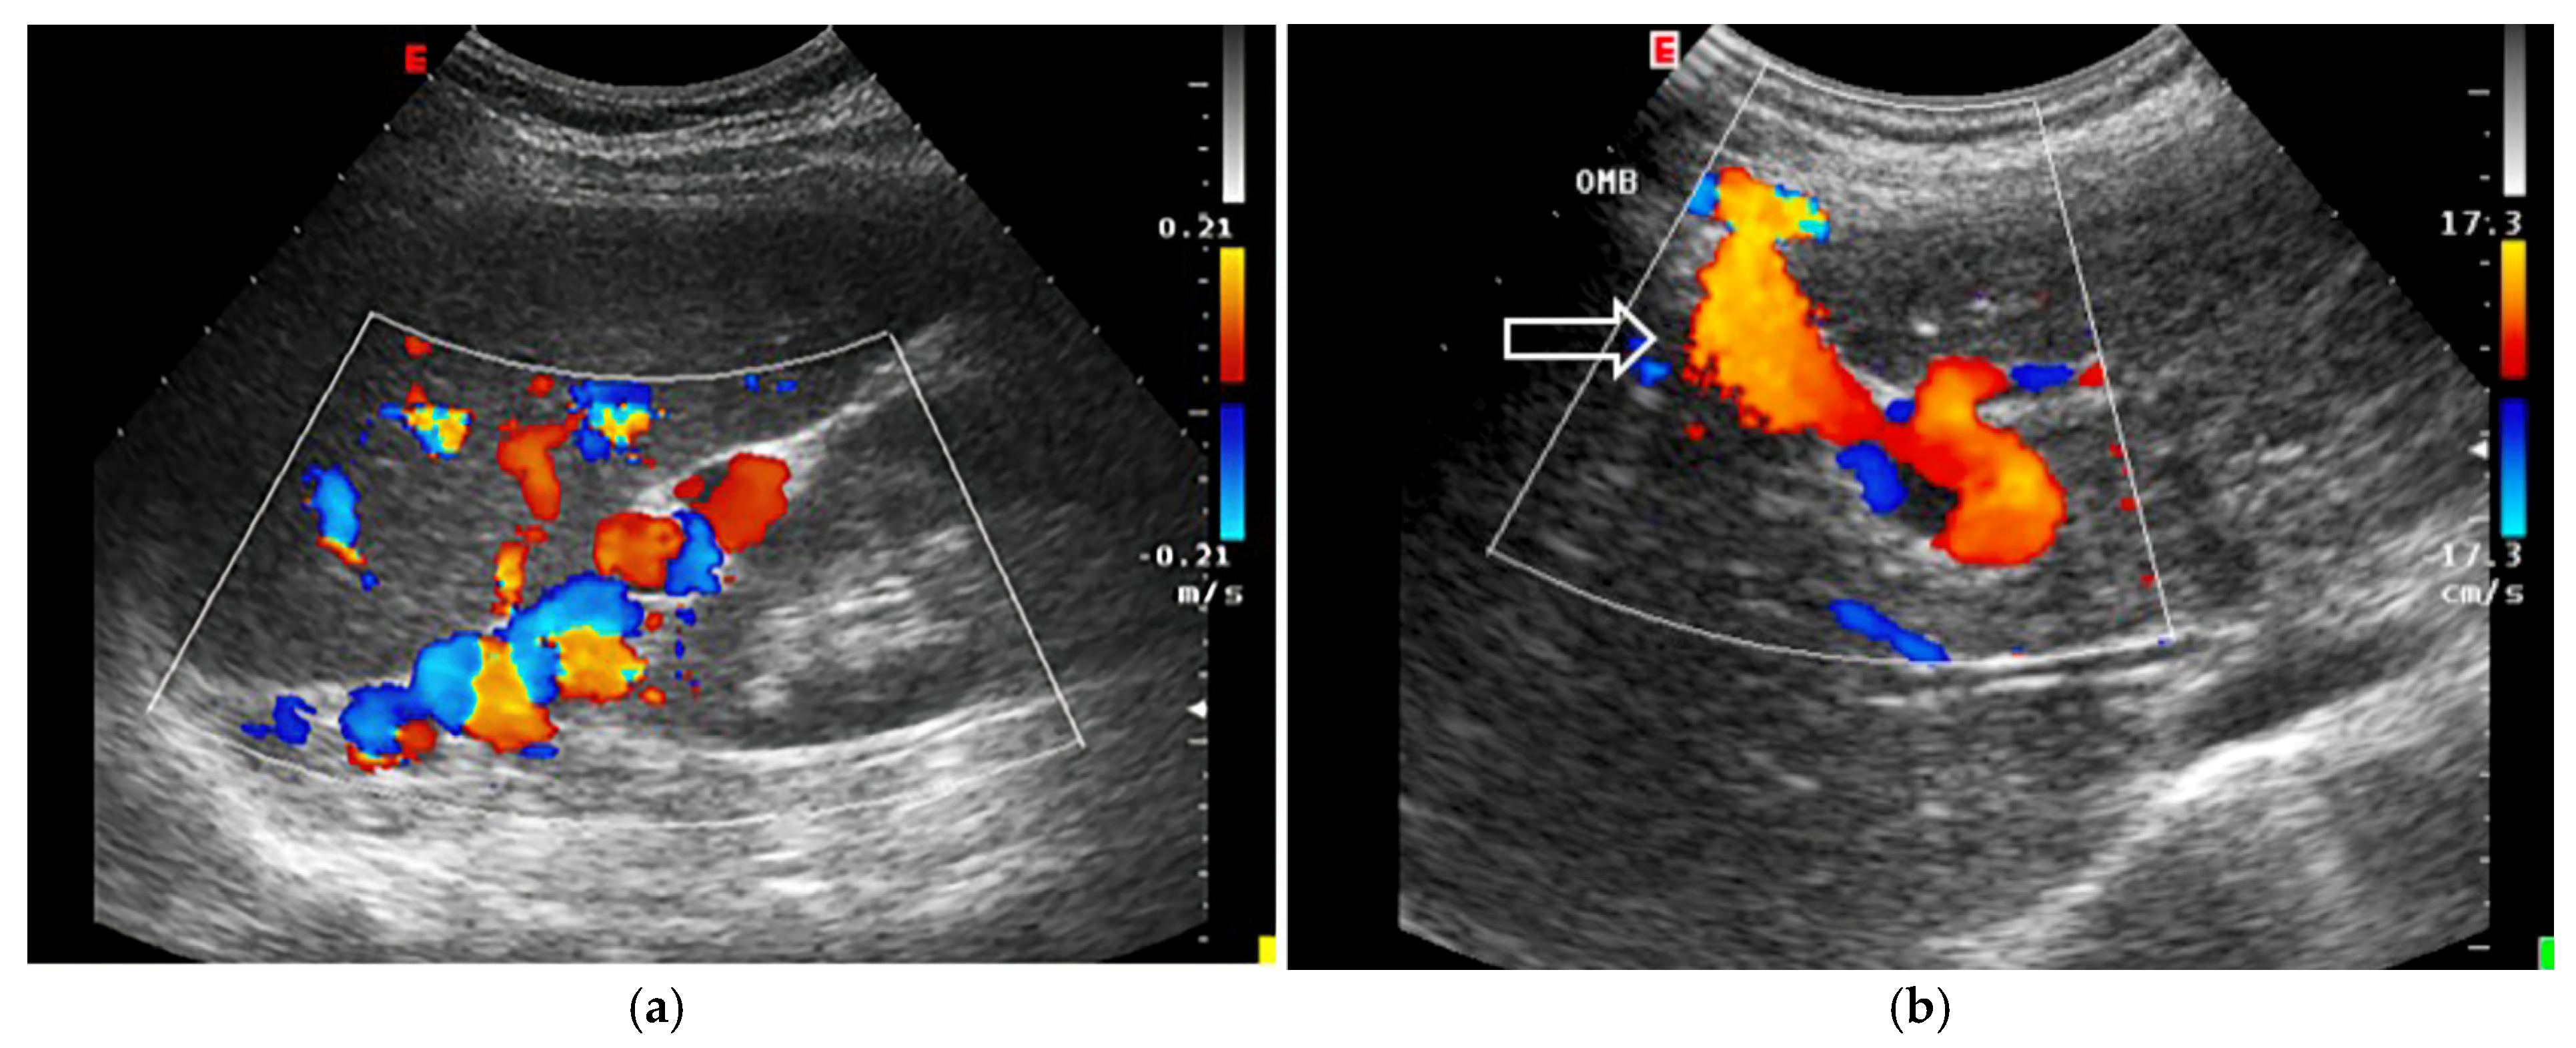

- Slow Portal Venous Flow: Slow flow occurs when back pressure restricts forward flow, typically indicating portal hypertension. In these cases, peak velocity is less than 16 cm/s [106]. Causes of portal hypertension include cirrhosis, portal vein thrombosis (prehepatic), and right-sided heart failure (posthepatic). The most specific findings include the development of portosystemic shunts (like a recanalized umbilical vein) and slow or reversed (hepatofugal) flow.

- Hepatofugal (Retrograde) Flow: Hepatofugal flow happens when the pressure in the portal vein exceeds that of the liver, causing flow to reverse and appear below the baseline. This is another indicator of portal hypertension, which can be caused by various conditions, including cirrhosis, right-sided heart failure and other portal vein obstructions [107] (Figure 9).Figure 9. (A) Increased pulsatility due to arteriovenous shunting in a case of hereditary haemorrhagic telangiectasia; (B) Reduced Portal Flow in a case of cirrhosis (C) Hepatofugal Flow of Portal Vein is a late sign of Portal Hypertension. It happens when the pressure in the portal vein exceeds that of the liver, causing flow to reverse and appear below the baseline. This is another indicator of portal hypertension, which can be caused by various conditions, including cirrhosis, right-sided heart failure and other portal vein obstructions.Figure 9. (A) Increased pulsatility due to arteriovenous shunting in a case of hereditary haemorrhagic telangiectasia; (B) Reduced Portal Flow in a case of cirrhosis (C) Hepatofugal Flow of Portal Vein is a late sign of Portal Hypertension. It happens when the pressure in the portal vein exceeds that of the liver, causing flow to reverse and appear below the baseline. This is another indicator of portal hypertension, which can be caused by various conditions, including cirrhosis, right-sided heart failure and other portal vein obstructions.

- Portal Vein Doppler: Normal portal vein flow is continuous, but severe venous congestion can cause pulsatility in the portal circulation. The pulsatility fraction (PVPF: [(Vmax − Vmin)/Vmax] × 100) quantifies this, with values above 30% indicating mild abnormalities and above 50% suggesting severe congestion [57]. Elevated PVPF is a strong predictor of acute kidney injury in post-cardiac surgery patients.